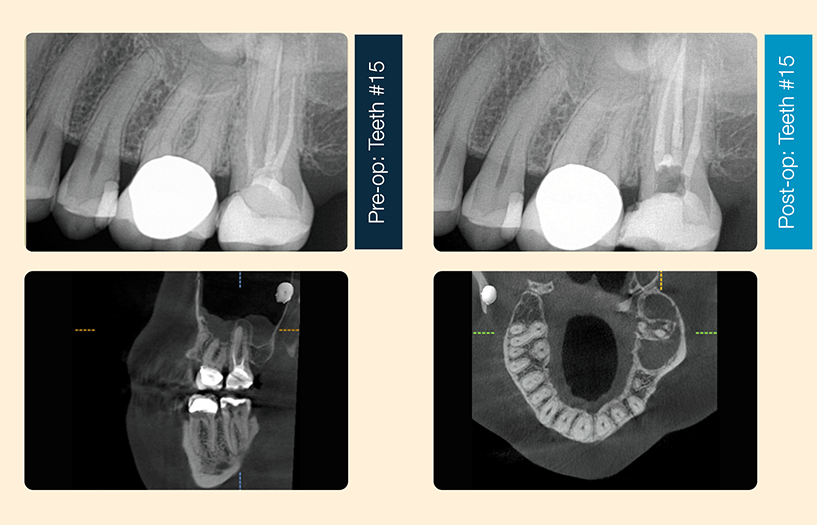

Tooth #15 Retreatment with interim calcium hydroxide. RCT #15 was initially completed 2 years ago in another office. The patient presented to me symptomatic, with a throbbing ache in the upper left quadrant. Tooth #15 was +++percussion, +++palpation, and ++bite, mobility and probings were WNL. On the preop CBCT, there is an apical lucency associated with #15 and mucositis of the maxillary sinus. Prior root canal fills were short and inadequate. I initiated retreatment and achieved patencies on all canals. At the second visit 2 weeks later, the patient was asymptomatic and I obturated with gutta-percha and BioRoot Flow Sealer, with the warm vertical technique.

I prefer the warm vertical technique because canals are not circular, hollow tubes. I like to sear down the gutta-percha with heat, compact the gutta-percha to fit the canal shape as best as I can, pushing the biocompatible and bioactive sealer into all the spaces within. I like the BioRoot Flow for my technique because it is not as radiodense as other sealers I have used, allowing me to differentiate between gutta-percha and sealer. This is illustrated in the case I shared above, the sealer puff of the palatal canal is less dense than the gutta-percha.